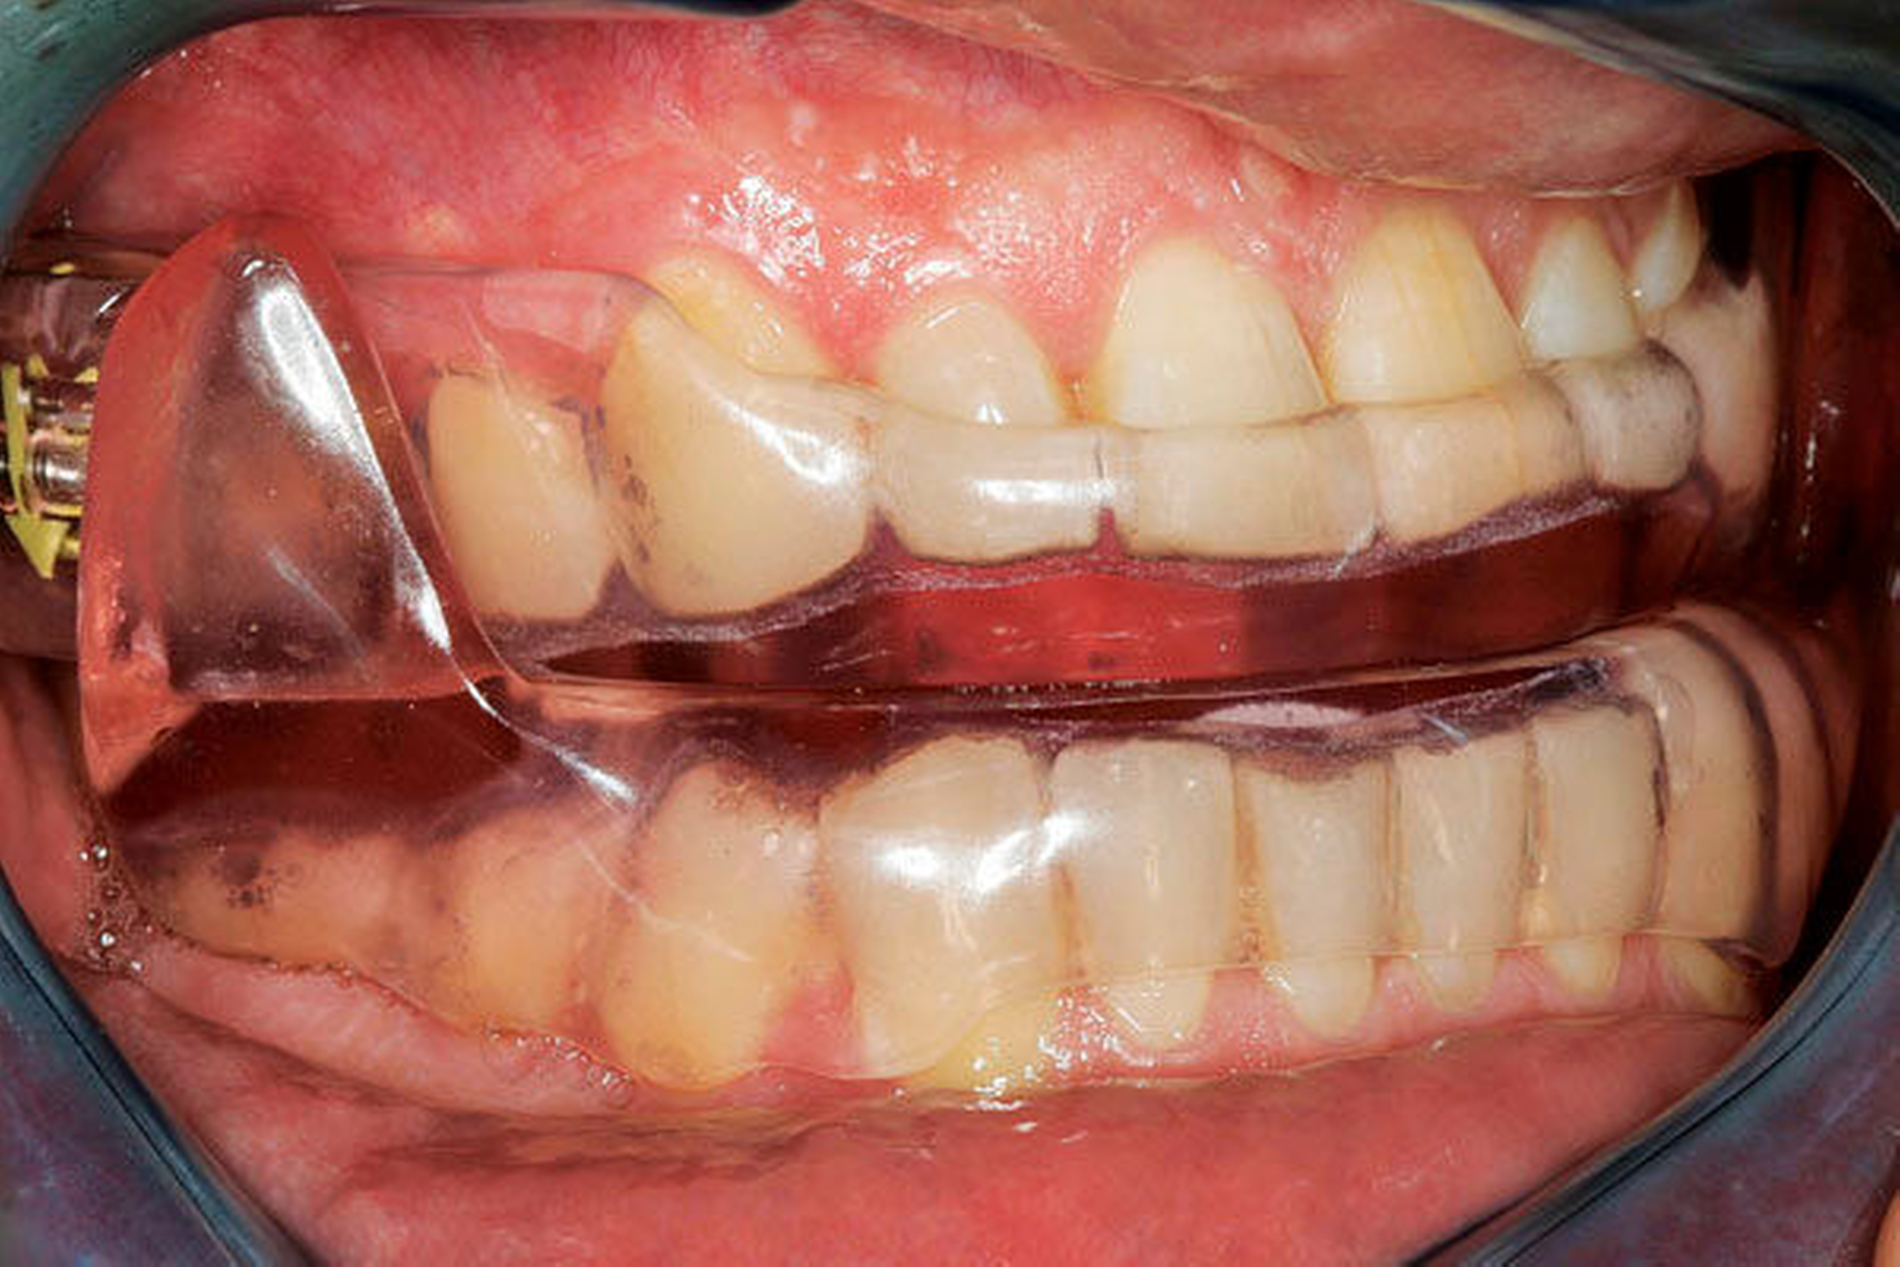

Okklusionsschienen gelten als reversible okklusale Ma ß nahmen, die eher symptomatisch eingesetzt den Abrieb der Z ä hne bei Schlafbruxismus verhindern helfen (Abbildung 4). Nachgewiesen werden konnte auch eine Reduktion der Kaumuskelaktivit ä t durch Schienen, dies jedoch nicht regel- und dauerhaft [Guaita et al., 2016; Manfredini et al., 2015]. Vielmehr wird eine intermittierende Trageweise empfohlen, um diesen Effekt auf die Muskulatur zu erzielen [Jokubauskas et al., 2018]. Die Wirkung der Schiene beruht auf einer Veränderung neuromuskulärer Reflexe und einer veränderten Rekrutierung von Muskelfasern durch die veränderte Okklusion [Ispirgil et al., 2018]. Treten jedoch Gewöhnungseffekte auf, verliert sich dieser Effekt.

Es werden eher harte als weiche Schienen empfohlen, da sie ein geringeres Risiko für Zahnfehlstellungen aufweisen. Zudem ließ sich bei weichen Schienen ein aktivitätssteigender Effekt auf die Muskulatur nachweisen [Lobbezoo et al., 2008; Macedo et al., 2007]. Am h ä ufigsten wurden Oberkieferschienen untersucht. Ein klares Konzept für die okklusale Gestaltung in Statik und Dynamik konnte aus den Studien nicht abgeleitet werden. Dickere Schienen (6 mm) zeigten einen geringeren Effekt auf Bruxismus als weniger dicke (3 mm) [Manfredini et al., 2015]. Ein horizontaler Frontzahn-Jig erwies sich als effektiv zur Minderung der Muskelaktivität. Eine längerfristige Tragedauer kann jedoch nicht empfohlen werden, da ungewollte Zahnstellungsveränderungen auftreten können [Stapelmann et al., 2008].

Bimaxilläre Schienen, die den Unterkiefer protrusiv stellen (UPS) reduzierten die Kaumuskelaktivität besser als Zentrikschienen. Mit dem Einsatz dieser Schienen bei Patienten mit Bruxismus und obstruktiver Schlafapnoe lässt sich zeitgleich die SBAS als relevanter Kofaktor behandeln [Lobbezoo et al., 2008; Singh et al., 2015; Jokubauskas et al., 2018].

- Im Rahmen der zahnärztlichen Behandlung von Schlafbruxismus können Schienen zum Schutz der Zähne im Schlaf eingegliedert werden, um durch die Unterbrechung der Zahn-zu-Zahn-Kontakte zuverlässig vor übermäßiger Attrition zu schützen [Lobbezoo et al., 2008; Macedo et al., 2007; Carra et al., 2012].

- Schienen können zur vorübergehenden Reduktion der Aktivität von Schlafbruxismus eingesetzt werden [Guaita et al., 2016; Ispirgil et al., 2018; Stapelmann et al., 2008; Singh et al., 2015].

- Aufgrund der geringsten Nebeneffekte sollten über einen längeren Zeitraum harte Schienen verwendet werden, die alle Zähne bedecken [Lobbezoo et al., 2008; Macedo et al., 2007].

- Wenn Bruxismus bei Patienten mit einer SBAS auftritt, können bimaxilläre Unterkiefer-Protrusionsschienen (UPS) erwogen werden (siehe S3-Leitlinie „Nicht erholsamer Schlaf“ aus 2017, AWMF-Register Nr. 063/001) [Manfredini et al., 2015; Singh et al., 2015; Huynh et al., 2006].